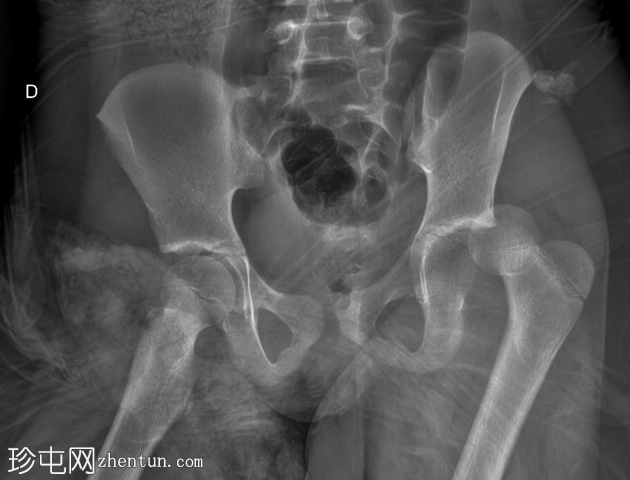

X线片

2.png

闭合复位后立即进行X线检查。

股骨头复位,左侧髋关节间隙恢复正常。